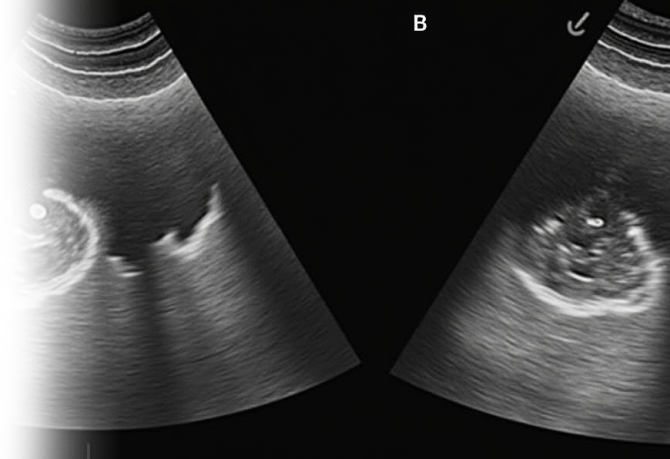

УЗИ плевральной области – метод диагностики, позволяющий оценить состояние пространства между листками плевры, окружающими легкое. Также эта процедура играет ключевую роль в контроле проведения биопсии и выявлении различных патологий.

Ультразвуковое исследование плевральной полости назначается при различных заболеваниях, таких как воспалительные процессы, опухоли, травмы и другие патологии, затрагивающие область грудной клетки. Неотложность и точность результатов ультразвукового исследования плевральной полости делают его необходимым звеном в комплексной диагностике заболеваний органов дыхания.

Благодаря ультразвуковой технике врачи получают высококачественное изображение плевральной полости, что позволяет выявить даже мельчайшие изменения в тканях.